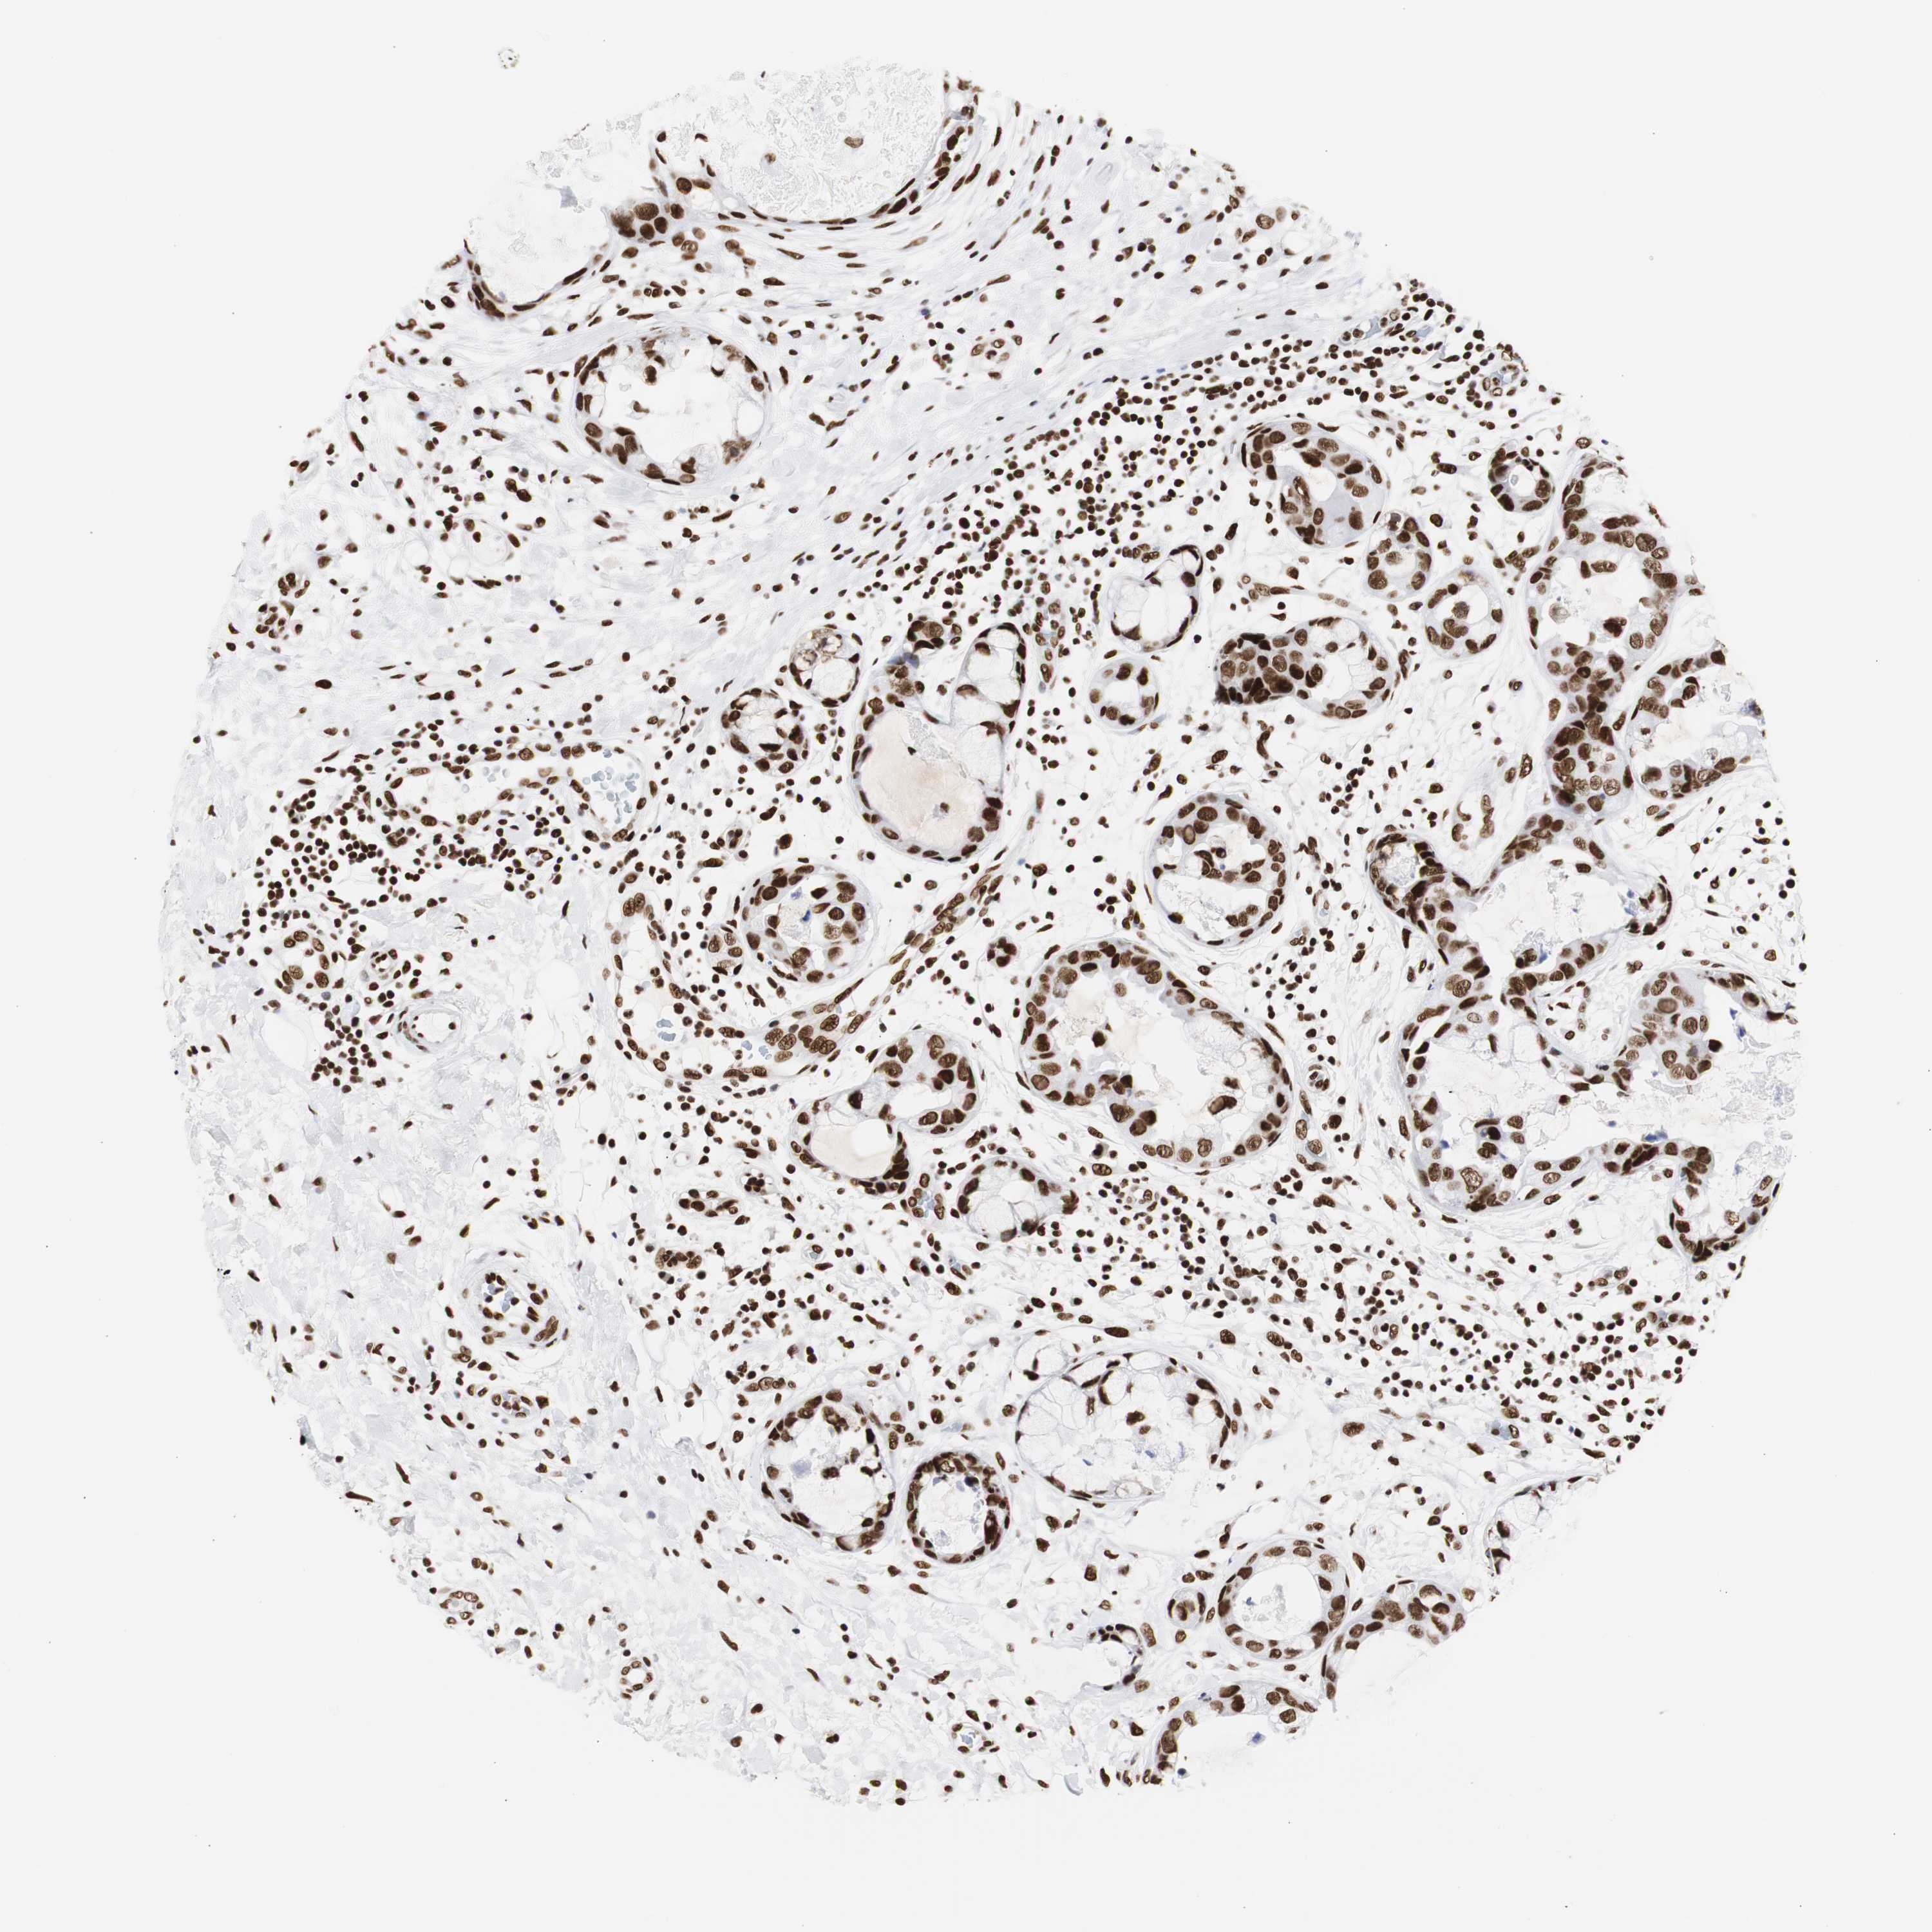

BRCA TCGA BRCA VALIDATION PROTEIN EXPRESSION